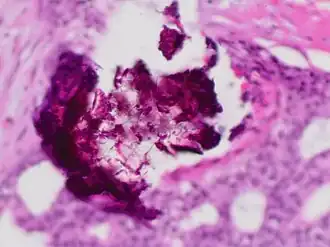

Calcium phosphate is the usual constitution of microcalcifications of the breast, particularly dystrophic calcifications. Microcalcifications as can be seen on mammography can be an early sign of breast cancer. Based on morphology, it is possible to classify by radiography how likely microcalcifications are to indicate cancer.[8]

Histopathology of dystrophic calcium phosphate microcalcifications in ductal carcinoma in situ (DCIS) of the breast, H&E stain.

Histopathology of dystrophic calcium phosphate microcalcifications in ductal carcinoma in situ (DCIS) of the breast, H&E stain.